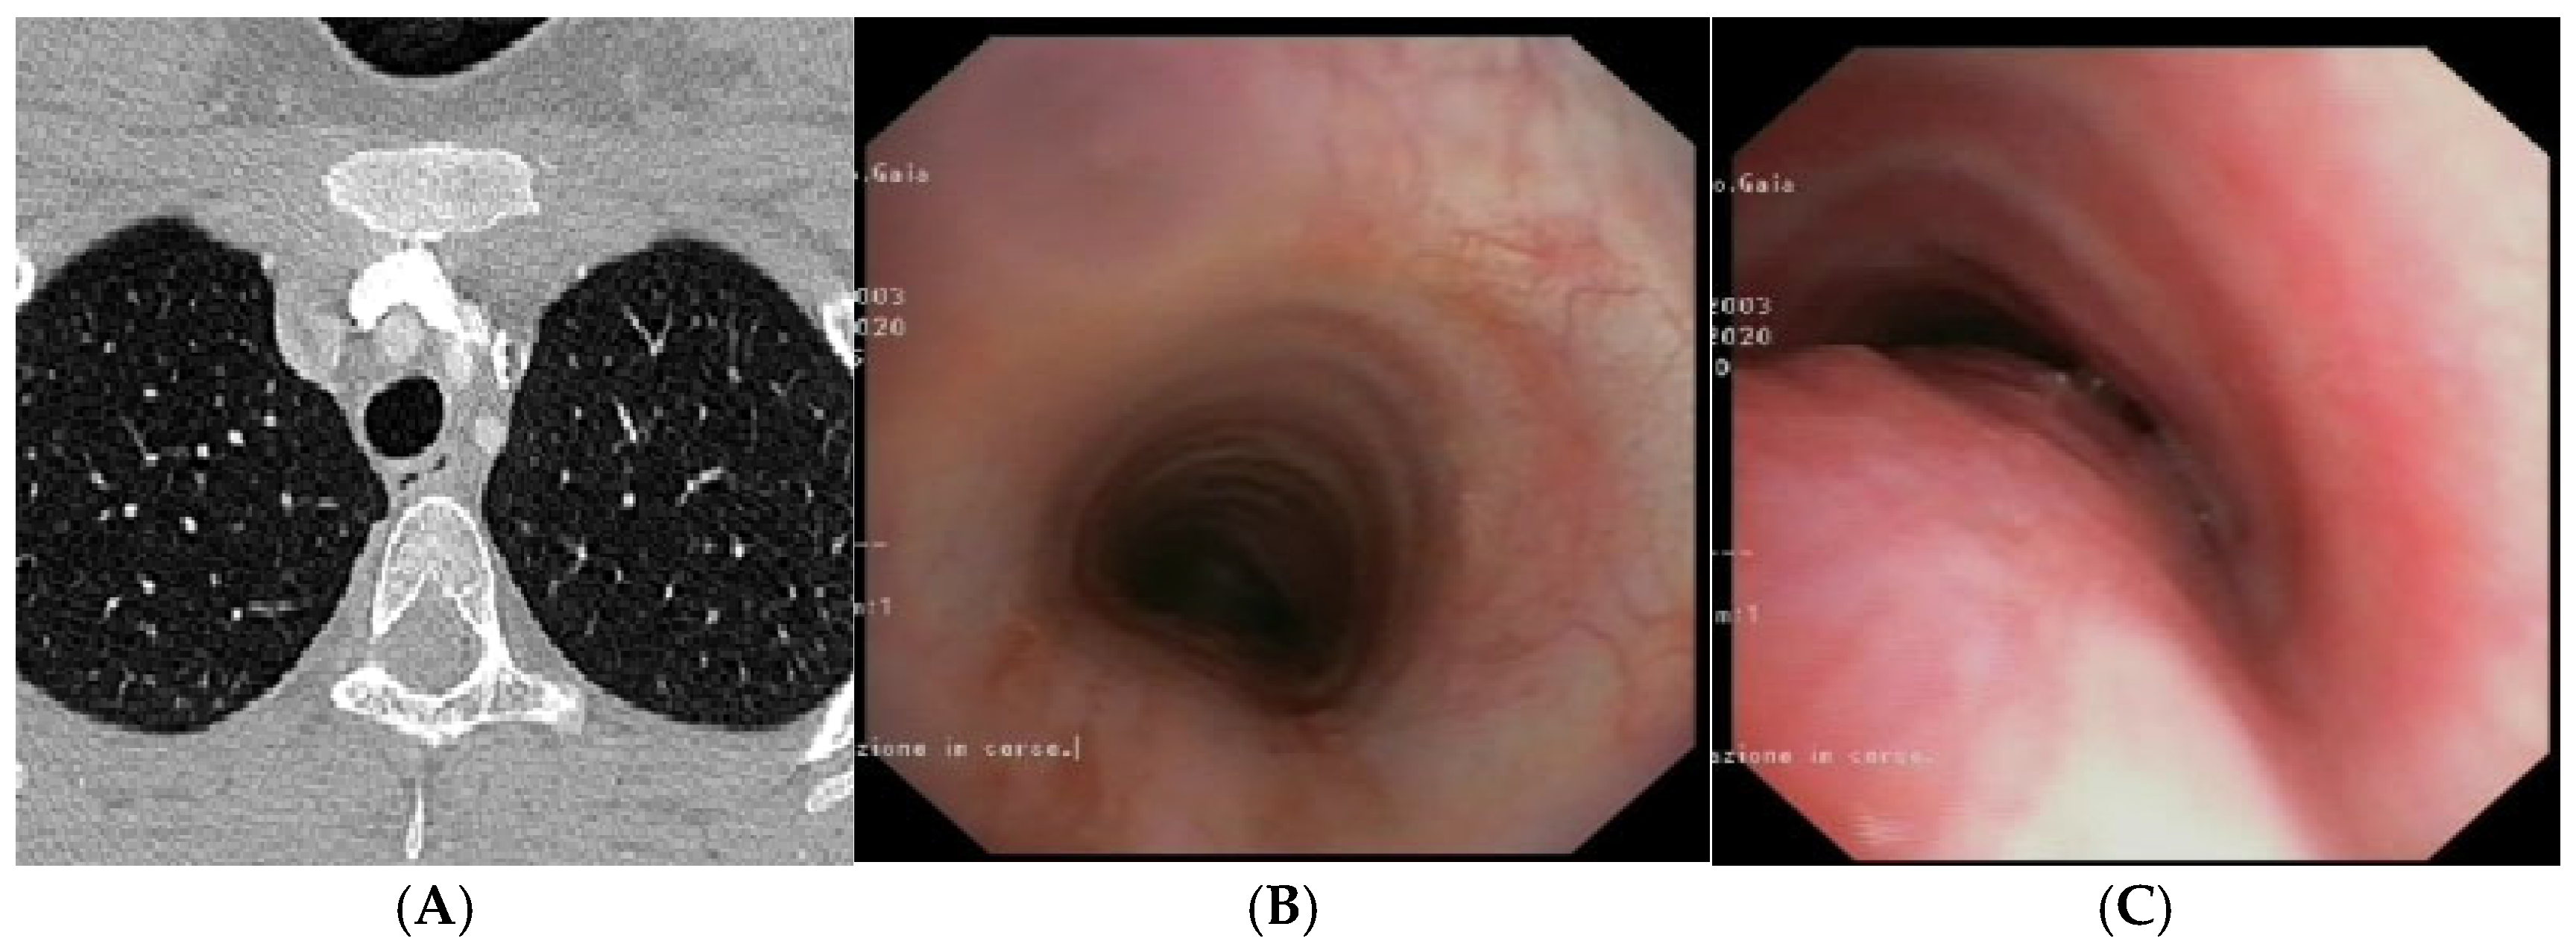

Figure 3.

A) Chest CT with CM: tracheal lumen only slightly deformed at the junction with the IA. Fig. B) SVBS, as CT, shows only slight extrinsic compression at the junction of the IA. Fig. C) DVBS, when the patient attempts to cough by performing abdominal straining: hypermobility of the pars membranacea, with subtotal occlusion of the tracheal lumen at the level of even slight extrinsic compression. Abbreviations. CT: Computed Tomography; CM: Contrast Medium; IA: Innominate Artery; SVBS Static Videobronchoscopy; DVBS: Dynamic Videobronchoscopy.

The patient is discharged with bac”grou’d medical therapy: Inhaled corticosteroid and respiratory physiotherapy with Positive Expiratory Pressure (PEP) mask, clinical follow-up after 6 months.